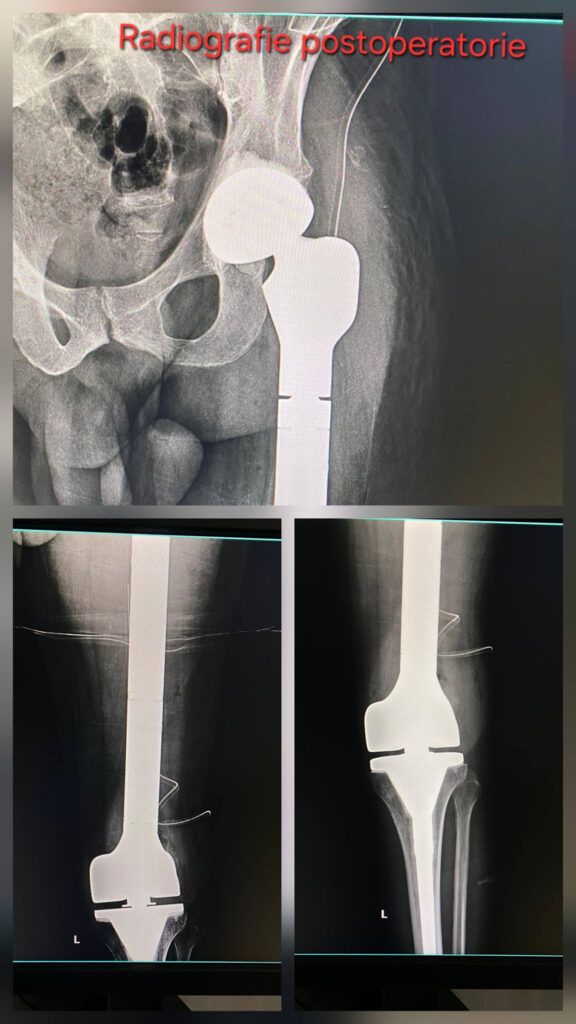

Spitalul Universitar de Urgență București a realizat cu succes o intervenție chirurgicală complexă de rezecție a femurului și implantare a unei megaproteze tumorale, oferind pacientului alternativa la amputație și recuperare funcțională optimă.

Procedura a constat în rezecția completă a femurului și înlocuirea acestuia cu o megaproteză tumorală personalizată, oferind pacientului șansa păstrării membrului și a unei recuperări funcționale semnificative.

Cazul a implicat un pacient tânăr, de 36 de ani, diagnosticat cu displazie fibroasă femurală și cu antecedente de fractură pe os patologic și artroplastie totală de șold. După mai multe intervenții și complicații, pacientul a fost transferat la SUUB pentru tratament specializat.

- Îndepărtarea integrală a femurului afectat

- Reconstrucția membrului inferior prin implantarea unei megaproteze tumorale personalizate